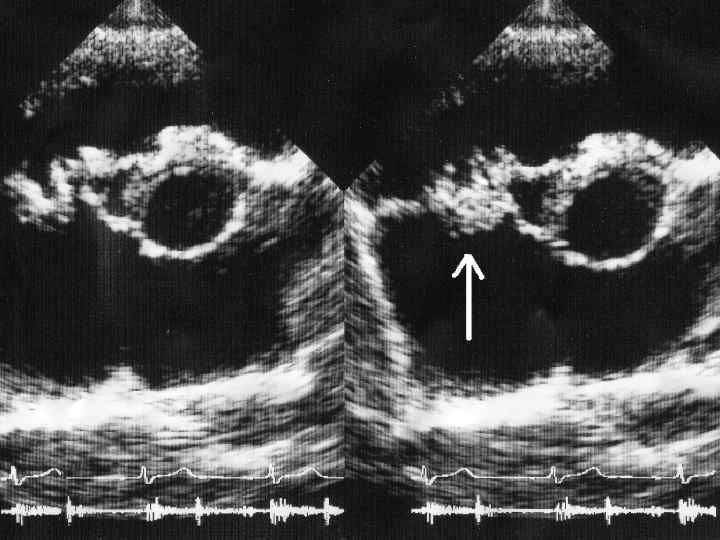

Поражение эндокарда: 1. Шум регургитации (аортальный клапан- диастолический, митральный/трикуспидальный- систолический) 2. Изменение звуковой картины при уже существующем пороке 3. ЭХО-КГ признаки регургитации, обнаружение вегетаций на клапане, пристеночном эндокарде

Диагностические критерии БОЛЬШИЕ: 1. Положительная гемокультура, характерная для ИЭ 2. Доказательства поражения эндокарда (наличие характерных. Эхо-КГ признаков) МАЛЫЕ: 1. Предшествующие заболевания сердца; 2. Лихорадка выше 38°C; 3. Сосудистые проявления 4. Иммунные нарушения 5. Микробиологическое подтверждение 6. Эхо. КГ-признаки, сходные с таковыми при ИЭ, но не соответствующие основным критериям.